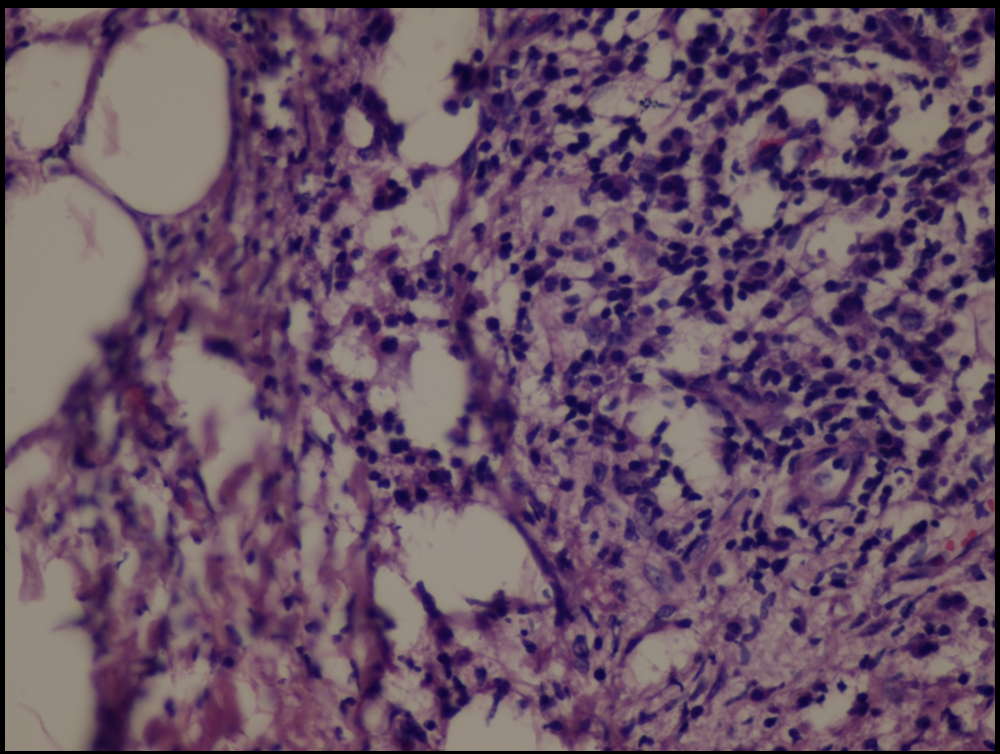

| Fig 7,8 :

The histologic sections of [patient (a), taken by punch

biopsy (4mm) from right thigh] revealed superficial and deep,

intense plasma cellular and lymphocytic infiltrate, primarily

in the lower dermis and fat septae with spillover to the

fat lobules. Fibrosis was present in the deep dermis and

in the fat. There was no vasculitis. (H&E stain; original

magnifications: x 40) |